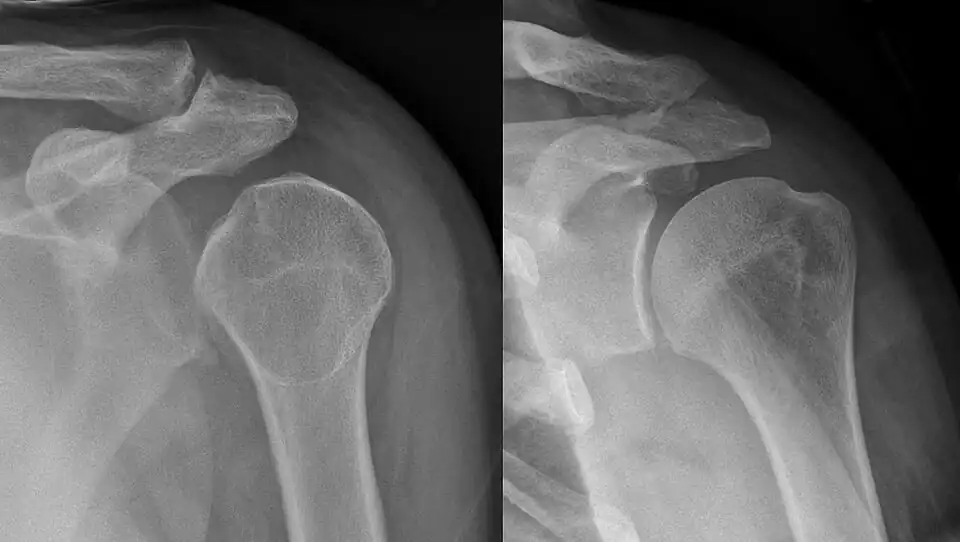

• Dislocated shoulder

• Anterior shoulder dislocation is the most common type of shoulder dislocation, accounting for at least 90% of shoulder dislocations.[5][35] Anterior shoulder dislocations have a recurrence rate around 39%, with younger age at initial dislocation, male sex, and joint hyperlaxity being risk factors for increased recurrence.[36]

• The incidence rate of anterior shoulder dislocations is roughly 23.1 to 23.9 per 100,000 person-years.[36][37] Young males have a higher incidence rate, roughly four times that of the overall population.[36]

• Recurrent anterior shoulder dislocations have a higher rate of labrum tears (Bankart lesion) and humerus fractures/dents (Hill-Sachs lesion) compared to initial dislocations.[38]

• Shoulder dislocations account for 45% of all dislocation visits to the emergency room.[5]